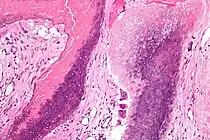

| Histopathology of pilomatricoma, high magnification, H&E stain, showing the characteristic components of basaloid cells and ghost cells. | |

The characteristic components of a pilomatricoma include a stroma of fibrovascular connective tissue surrounding irregularly shaped, lobulated islands containing basaloid cells (being darkly stained, round or elongated, with indistinct cell borders and minimal cytoplasm, with nuclei being round to ovoid, deeply basophilic and generally prominent nucleoli), which abruptly or gradually transitions into ghost cells (having abundant, pale, eosinophilic cytoplasm, well defined cell borders and a central clear area, but only faint traces of nuclear material), which in turn may transition into keratinaceous to amorphous necrosis.[11]

The presence of calcifications with foreign-body giant cells is common within the tumors.[12]